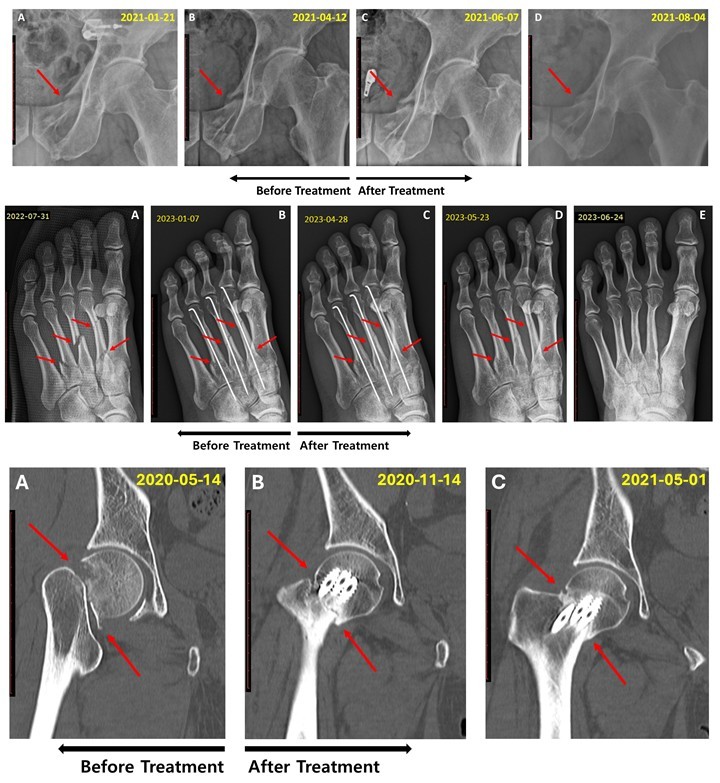

접골탕, 기존 치료 무반응인 지연유압 골절에 효과 확인

5개월 이상 장기 지연유합도 접골탕 치료 가능성 확인

[한의신문] 한국한의학연구원(원장 이진용·이하 한의학연)은 골절 치료 한약인 접골탕이 5~6개월 이상 지속된 골절 지연유합 환자들의 치료에 효과적이라는 연구 결과를 지난 24일 발표했다.

한의치료 사례의 과학적 검증을 지원하는 코어(KORE) 프로젝트의 일환으로 진행된 이번 연구는 국제 학술지인 ‘Frontiers in Endocrinology’(IF 4.6)에 지난달 30일 게재됐다.

한의학연 관계자는 연구결과 접골탕은 골반뼈, 다발성 중족골, 대퇴골 경부 골절 지연유합에서 효과를 보였다이번 연구는 기존에 알려진 접골탕의 골밀도 개선 효과와 3개월 이내 지연유합 치료 효과에서 더 나아가, 5~6개월 이상 지속된 난치성 지연유합에서도 효과가 있다고 설명했다.

한의학연에 따르면 연구에 보고된 접골탕은 당귀, 천궁, 속단 등 여러 한약재를 비압력 탕전방식으로 2시간 열수 추출한 한약이다.

또 접골탕의 주요 성분인 노다케닌(nodakenin)’은 골모세포 분화를 촉진하고 골흡수 세포 형성을 억제하는 이중 기전을 통해 골재생에 기여하며, ‘페룰산(ferulic acid)’은 혈관 내피 기능을 향상시켜 골절 부위의 혈액 공급을 개선하는 것으로 알려져 있다고 한의학연 관계자는 밝혔다.

연구책임자 양창섭 박사는 이번 연구는 기존 치료법으로 충분한 회복을 이루지 못한 장기 지연유합 환자들에게 접골탕이 효과적인 보완 치료 옵션이 될 수 있음을 보여준다특히 수술적 개입이 어려운 환자나 재수술을 고려해야 하는 상황에서 대안이 될 수 있다고 설명했다.